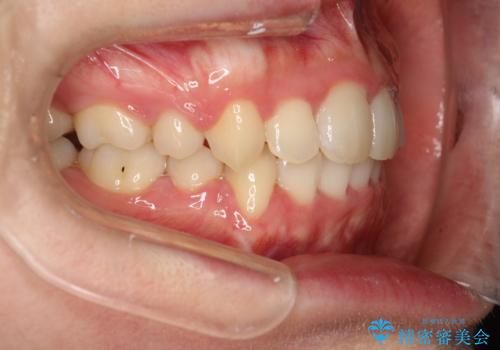

患者様が装置を早期に除去したいという希望もあり、少々下の前歯のがたつきが残った状態で矯正を終了しました。

全体的ながたつきがなくなり、見た目の印象がよくなりました。